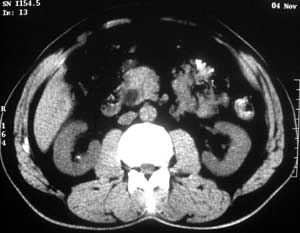

患者,男,57岁,梗阻性黄疸10余天。

这个病例胰头无明显增大,胆总管扩张明显而肝内胆管扩张更不明显,病程较短,

注意到十二指肠乳头明显突出,但尚光滑。分析以下可能性:

1、十二指肠乳头本身的病变,如乳头炎症;

2、急性乳头水肿,胆总管下端结石排石后乳头水肿;

3、壶腹部胆总管下端肿瘤累及十二指肠乳头。

十二指肠乳头粘膜慢性非特异性炎症